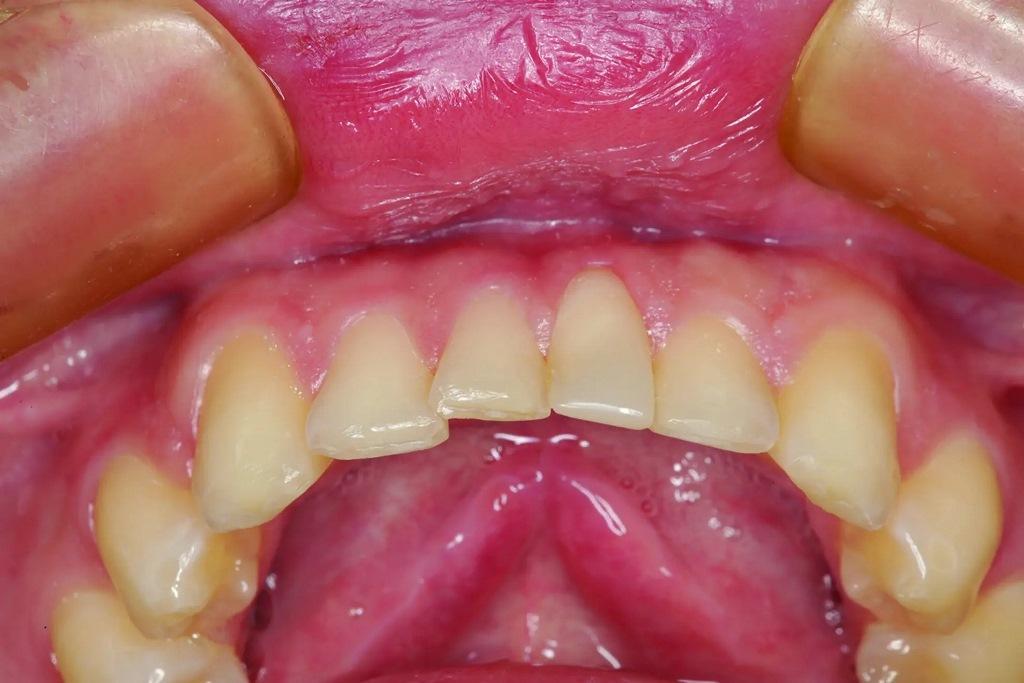

А как насчет выравнивания зубов-антагонистов? На режущих краях зубов 31 и 41 (фото 2) наблюдался чрезмерный износ. Со стороны резцов был виден значительный износ всех краев нижней челюсти из-за окклюзионного заболевания, которое часто наблюдается, но не лечится (фото 3). Также зуб 41 располагался на лицевой стороне таким образом, что при выступающей экскурсии он преждевременно соприкасался с небной поверхностью зуба 11, создавая дополнительную нагрузку как на небную поверхность, так и на резцовый край зуба 11, прежде чем соединиться с остальной частью переднего сегмента верхней челюсти. Это демонстрирует, что решение этих проблем реставрационными методами включает в себя нечто большее, чем просто исправление сколов композитной реставрации.

Фото 2: Зубы выступают вперед, что свидетельствует о чрезмерном износе зуба (41), расположенного напротив зуба 11, что указывает на гиперфункцию и повышенную функциональную нагрузку на восстановленную область.